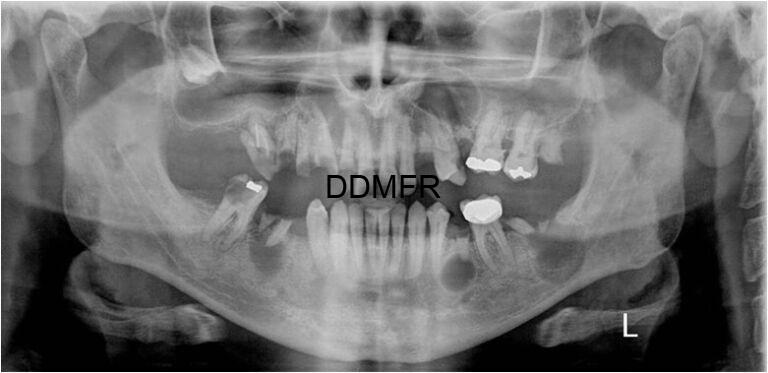

Πολλαπλές κύστεις των γνάθων .

- Δεν αποτελούν ξεχωριστή παθολογική οντότητα. Συνήθως είναι πολλαπλές ακρορριζικές κύστεις, ακρορριζικά κοκκιώματα ή οδοντογενείς κερατινοκύστεις.

- Πολλαπλές οδοντογενείς κερατινοκύστεις μπορεί να εμφανιστούν στο σύνδρομο πολλαπλών σπιλοειδών βασικοκυτταρικών καρκινωμάτων (σύνδρομο Gorlin-Goltz)